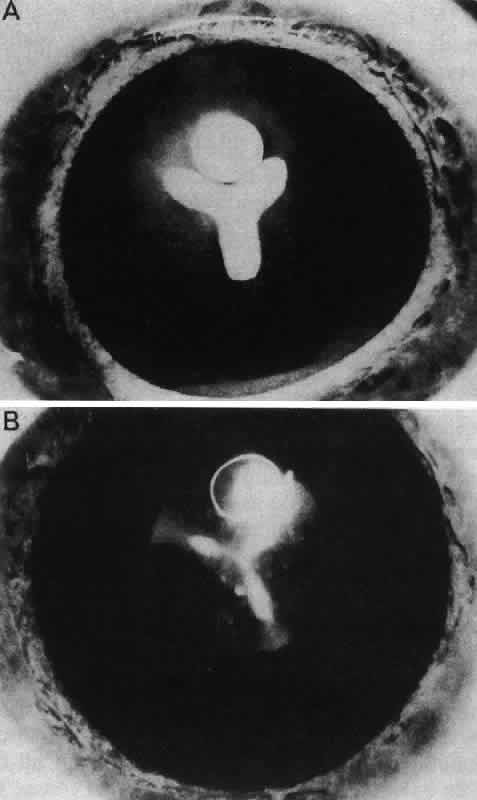

Fig. 21. A. Lens epithelial whole-mount preparation from a normal young adult lens showing the area of the meridional rows. B. the same area taken from a lens with a nuclear cataract. C. The meridional rows of a lens with a posterior subcapsular cataract showing the loss of organization and the posterior migration of cells. The dark strand is a zonule fiber. D. The meridional rows are completely disorganized at the equator in an epithelium taken from a mature steroid cataract. (Streeten BW, Eshaghian J: Human posterior subcapsular cataract. Arch Ophthalmol 96:1653, 1978)

Electron-microscopic analyses of the area of the meridional rows (i.e., where the lens fibers begin to internalize) reveal that adjacent cells enter the region in a staggered fashion, producing potential furrows between alternating cells (Fig. 20). This cadre may be responsible for the precise alignment of the cells as they enter the region. It has been hypothesized97 that the tension of the overlying capsule, in conjunction with the laterally placed and subjacent fibers, dictates the manner in which newly elongating cells align in the meridional rows. If this is indeed the case, it must then follow that an effect on any one of these parameters might result in “misdirected” fibergenesis and altered cytoarchitecture. It is interesting that the loss of meridional row alignment (Fig. 21) is associated with the development of a number of cataracts of varying causes in experimental animal,79,97,98 as well as in human,99 lenses. In the animal studies, it was shown that meridional row disorganization temporally precedes cataractogenesis. It remains to be determined whether there is a causal link between the loss of meridional row cytoarchitecture and the development of a number of types of cataract.